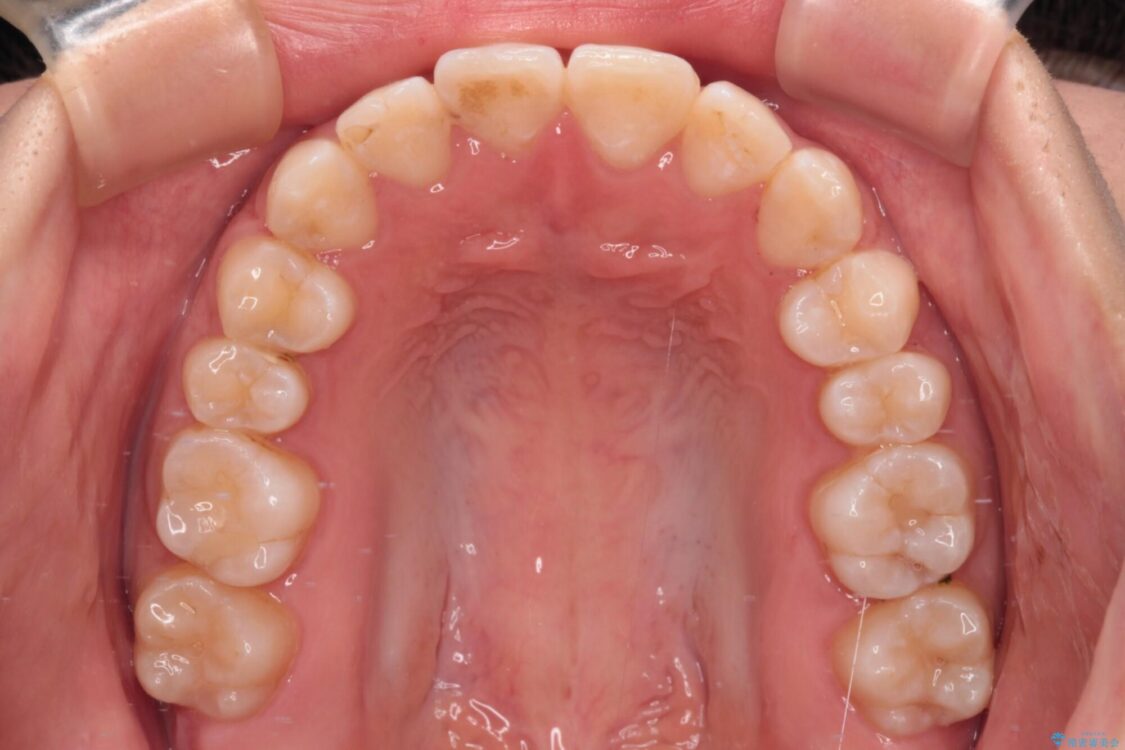

前歯のデコボコを気にして来院された患者様です。

治療前

• 【モニター】短期間で終わりたい ワイヤー装置での非抜歯矯正 治療前画像